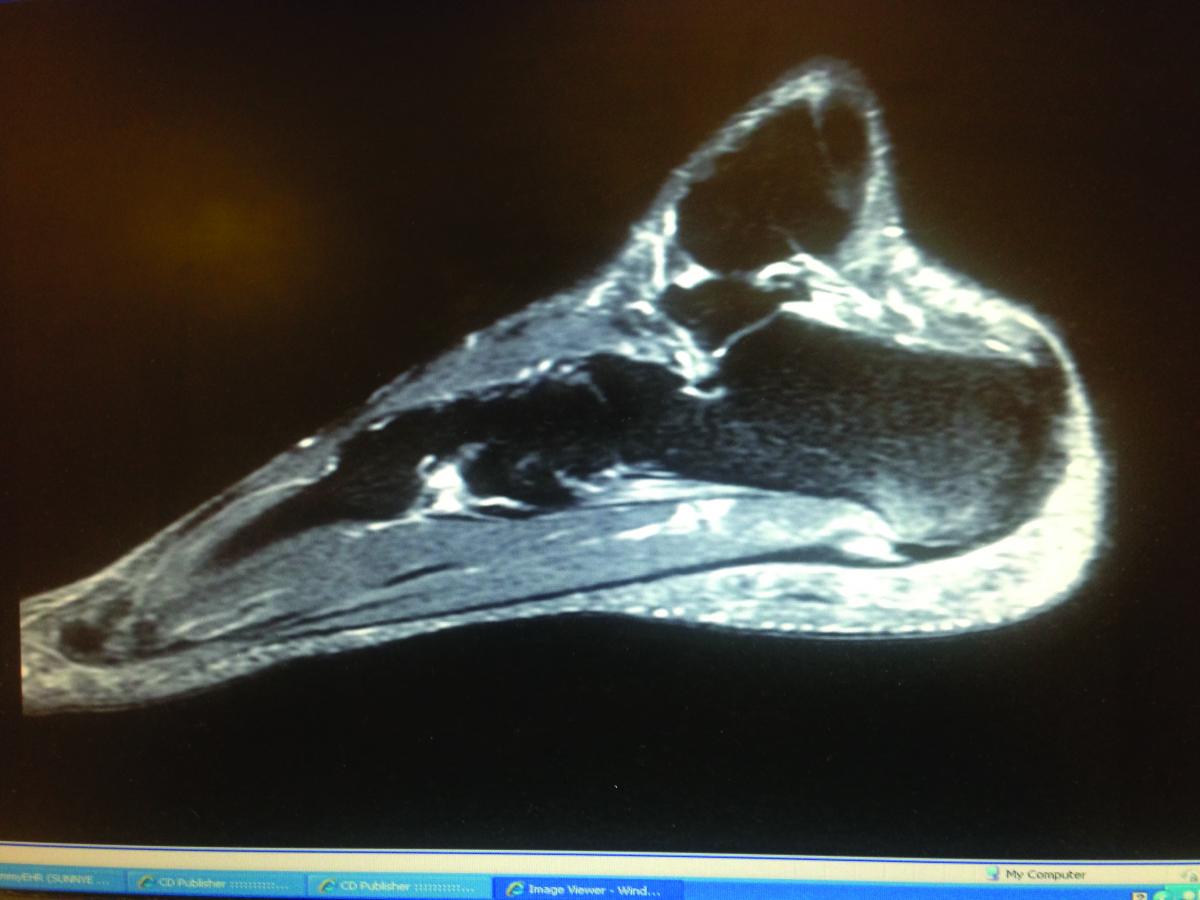

Notwithstanding, researchers had attributed mechanical overload as being the primary etiology of plantar fasciitis.14,15 Looking at the histopathlogy of the damaged plantar fascia in patients with plantar heel pain, Lemont and colleagues demonstrated evidence of tissue changes consistent with chronic degeneration: myxoid degeneration and fibroblast necrosis, chondroid metaplasia, angiofibroblastic proliferation, collagen degeneration, an altered ratio of Type III to Type I collagen, and an increased number of abnormal fibroblasts with mitochondrial defects.16

With the recognition that inflammation does not appear to be a dominant feature of plantar fasciitis, newer terminologies (such as “plantar fasciosis” or “plantar fasciopathy”) have emerged and are now in common use when referring to this condition.16,17 The absence of inflammation and the presence of degenerative changes have also been present with chronic tendon disorders.18 Authors have often attributed tendinopathy to tensile overload.19 Accordingly, podiatric physicians often attribute plantar “fasciopathy” to simple overload as well. This has led to a well-recognized mechanism in which failure of the medial arch of the foot or overload of the Achilles tendon will lead to increased tensile load on the plantar fascia.20

In an important paper, Wearing and coworkers present numerous challenges to the assumption that the histopathologic changes in plantar fasciopathy are the result of altered loading or increased tensile strain on the plantar aponeurosis due to abnormal arch mechanics.21 The authors show evidence that heel spurs may be the result of bending rather than traction loading of the insertion of the plantar aponeurosis on the calcaneus. These authors also note that with tendinosis, traction is not always a primary contributor as researchers have shown that other factors such as local ischemic changes as well as the formation of free radicals may cause degenerative changes. Wearing and colleagues demonstrate that gait studies of the kinetics and kinematics of patients with plantar fasciitis reveal conflicting and inconsistent results. Attributing plantar fasciopathy to a failure of arch mechanics leading to excessive traction may be overlooking other etiologic factors. They point out that one must also consider bending, compression and shear forces. This may be one explanation for the conflicting results of foot orthotic therapy in treating patients with plantar heel pain.